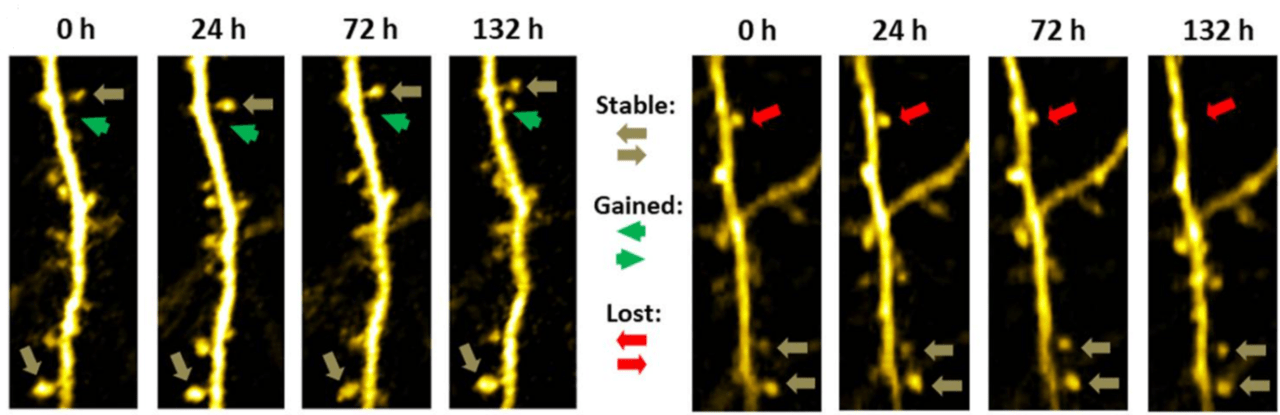

We use two-photon microscopy to measure dendritic spine turnover in the most physiologically relevant model system: the brains of awake, behaving mice. Typical readouts are dendritic spine density, formation rate, elimination rate, mobile spine fraction, and net change. Our assay is uniquely suited to assess drug efficacy or mode of action longitudinally or to characterize mouse disease models. We can combine this assay with video recordings (e.g. of pupil dilation) or simple behavioral readouts.

Two-photon microscopy enables high-resolution imaging of living tissue at great imaging depth with low phototoxicity (for more information, please visit our two-photon page). For that reason, it is the only technology to image dendritic spines and quantify their dynamics (turnover) in the brains of living mice. Since two-photon microscopy is non-invasive, the same part of the brain in the same animal can be re-examined for up to several months. In addition, control data can be obtained from the same animal, which reduces variability and allows smaller group sizes. Therefore, performing dendritic spine turnover experiments using two-photon microscopy Reduces the number of animals and Refines data quality. This complies with the 3R principle for the use of experimental animals.

Neurotar is the world’s leading commercial service provider of in vivo two-photon brain imaging, the only technique to visualize dendritic spines and quantify their dynamics (turnover) in the brains of living mice. Our expert team has completed multiple dendritic spine turnover studies for a variety of companies from all over the globe. Typical readouts for these studies are dendritic spine density, formation rate, elimination rate, mobile spine fraction, and net change.

- 3-5 imaging sessions: baseline at 0 h, 2-4 imaging sessions over several days, weeks, or months

- We quantify turnover of at least 150 individual dendritic spines per animal